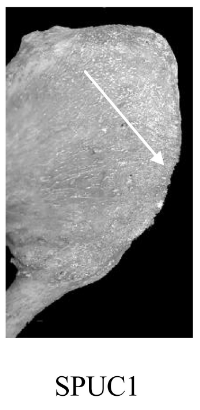

Bord postérieur (SPUC)

Aspect de la lèvre du bord postérieur de la surface articulaire.